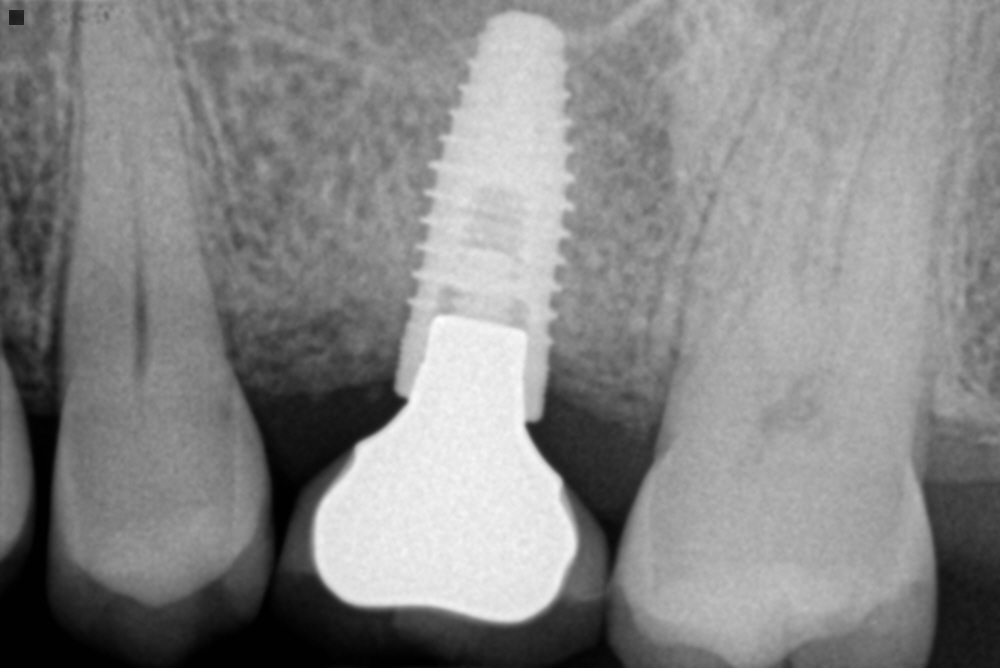

Stomatologiyanın təməl vəzifələrindən biri, itirilmiş dişlərin funksiya və estetik olaraq təbiiyə ən yaxın şəkildə bərpa edə bilməkdir. Dişsizliyin estetik və funksional olaraq yüksək səviyyədə reabilitasiyası, pasiyentlərin çeynəmə, danışma və gülmə kimi funksiyalarını qüsursuz icra edə bilməsi baxımından çox önəmlidir. Diş implantları xüsusi texnologiya hazırlanaraq, itirilmiş dişin bərpası üçün tətbiq edilən süni diş kökləridir. Bu metod təbiiyə ən yaxın bərpanı vəd edən müalicə metodu kimi uzun illərdən bəri beynəlxalq miqyasda geniş tətbiq olunur. İmplantasiya, bu işin peşəkarı yüksək ixtisaslı mütəxəssis tərəfindən qısa bir müddət davam edən prosedur vasitəsilə ağrısız, qısa müddətə və həyati funksiyaların məhdudlaşmaması şərti ilə həyata keçirilən müalicə üsuludur.

Dental implantlar əsasən titandan hazırlanır. Bu materialdan hazırlanmasının ən başlıca səbəbləri, bu metalın orqanizm tərəfindən rədd edilməməsi, heç bir allergik reaksiyaya səbəb olmaması və bu təyinat üçün yetərli möhkəmliyinin olmasıdır. Diş implantları vasitəsilə, tək diş əksikliyindən, çoxsaylı diş əksikliyi və tam dişsizlik halları funksional və estetik bərpa edilə bilir. İmplantın üzərinə hazırlanan diş konstruksiyaları müvafiq vəziyyətlərdə implantların tətbiqi ilə eyni gündə və ya müəyyən bir sağalma dövrünün keçməsindən sonra hazırlana bilir. İmplantların istismar müddəti, doğru planlama və icraat həyata keçirildiyində, eyni zamanda yetərli gigiyenik qulluq şəraitində bir neçə on illik bir periyodu əhatə edə bilir.